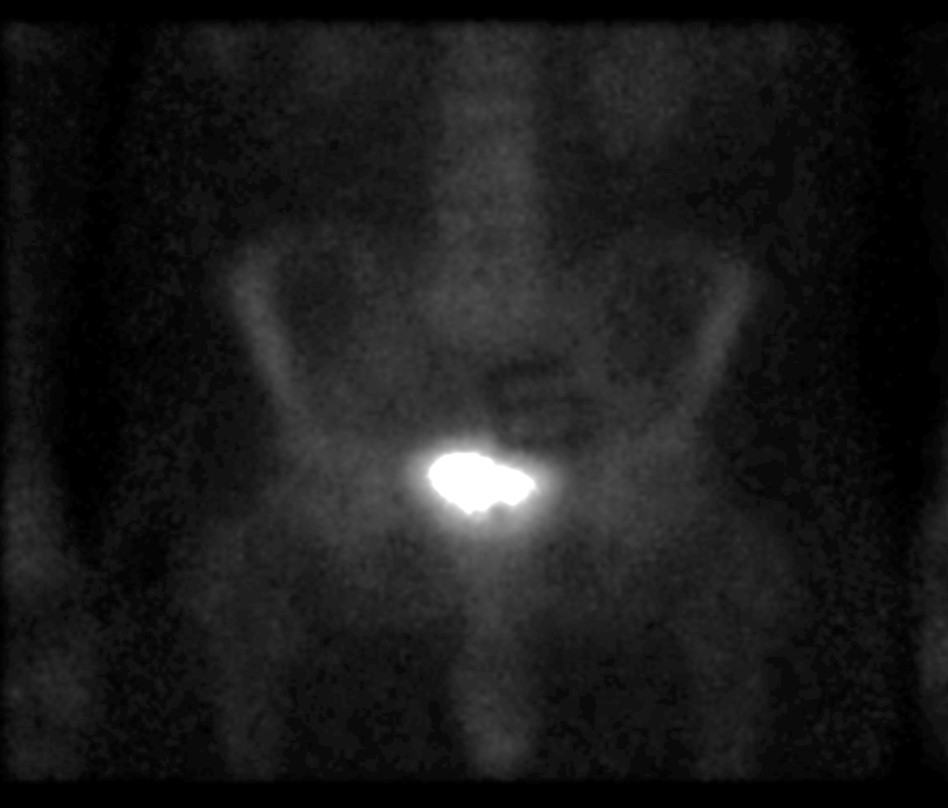

60 year-old man with history of lung cancer and left hip arthroplasty suffered from stiffness in the left hip region. Axial CT, FDG PET, fused axial, and coronal PET-CT demonstrates increased uptake of FDG in heterotopic ossification in the musculature of the left thigh. |